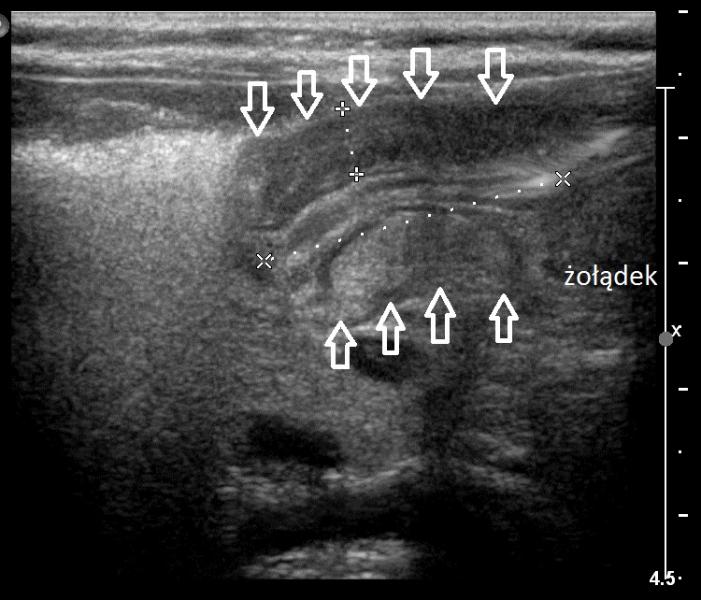

2-miesięczny chłopiec z chlustającymi wymiotami.

Przypadek 5: 2-miesięczny chłopiec z chlustającymi wymiotami.

Rozpoznanie: W badaniu usg - pogrubiała mięśniówka odźwernika, kanał odźwiernika szczelinowaty. Przerostowe zwężenie odźwiernika (pylorostenoza).